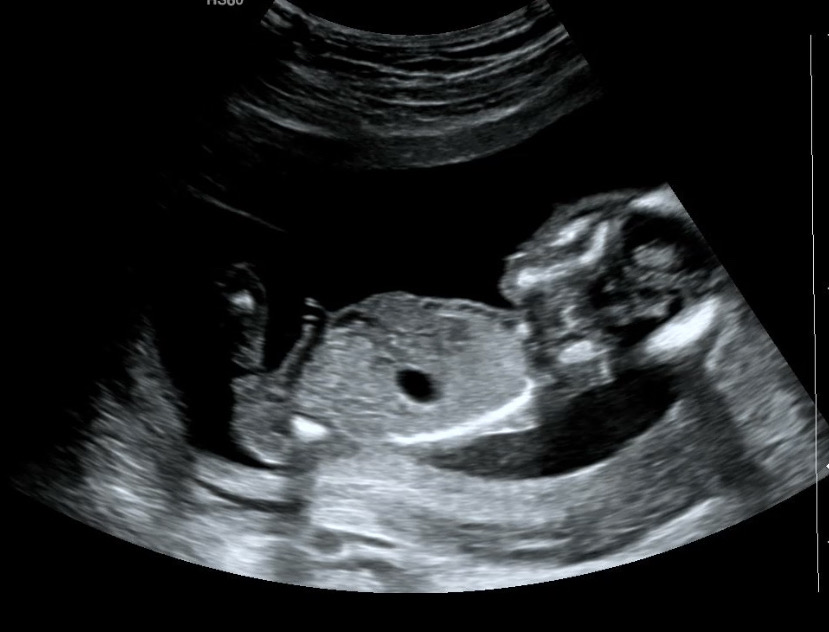

15주 딸?

딸이 맞을까요 ㅎㅎㅎ